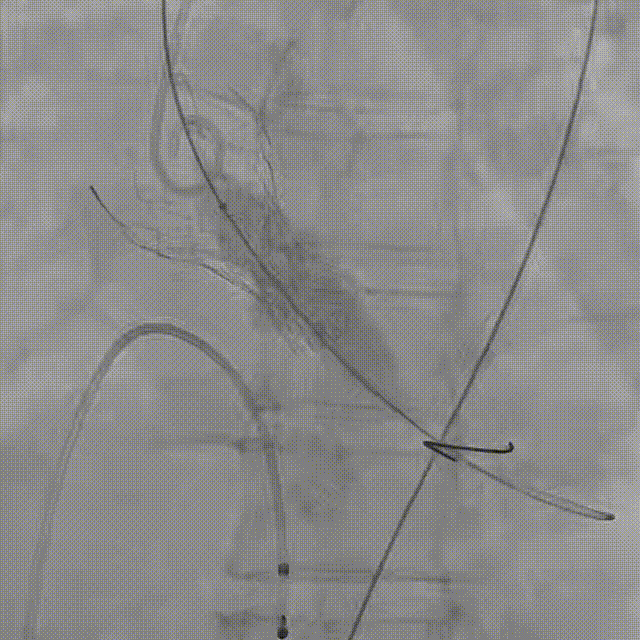

患者病史 主诉:发作性胸闷憋喘半年,加重伴呼吸困难2周。 现病史:患者半年前无明显诱因出现胸闷、憋喘,伴有下肢水肿,2周前上述症状明显加重,夜间不能平卧,痰中带血丝,为进一步诊治再次来我院,门诊以"心力衰竭"收入院。 既往史:肾功能不全、心房颤动 心脏超声提示:LVEF:0.54 1.主动脉瓣病变;2.主动脉瓣狭窄(重度)并反流(中度);3左室壁节段性运动不良;4.升主动脉扩张、双房扩大、左室肥厚;5.二尖瓣硬化并反流(中度);6.三尖瓣反流(轻-中度);7.肺动脉瓣反流;8.肺动脉高压(轻度)PGmean=105mmHg,Vmax=635cm/s,瓣口面积0.27cm²。 术前CT评估 Type0型二叶瓣,重度钙化,钙化集中在瓣叶游离缘,右冠窦为著;左冠高度11.8mm,由于左冠窦部空间较小,左冠风险较高, 升主动脉扩张,最宽处50.5mm;主动脉瓣环水平夹角61.5°,横位心。主动脉弓角77.6°,锐角弓,外周入路在腹主及髂总处有大量散状钙化,胸主处有81.6°的迂曲。 手术策略 推荐右侧股动脉为主入路,左侧股动脉为辅入路,送snare辅助过弯,使用18F大鞘,推荐预装ProStyle A® AV23瓣膜,20mm球囊预扩,初始定位对齐真实瓣环瓣上5mm超高位初始定位释放,释放过程中使瓣膜自然下滑,到工作位观察瓣膜形态,最终理想位置0-瓣下3mm。 手术过程 Step1:右侧股动脉为主入路、左侧股动脉为辅入路,成功穿刺并送入 18F 大鞘; Step2:主动脉根部造影,瓣口限制重 Step3:Type 0 型二叶瓣畸形合并重度钙化,患者瓣口狭窄严重,同时横位心,不仅导丝跨瓣困难,导管更难进入;术者凭借精湛操作,将导丝顺利跨瓣,反复微调导管角度,最终导管顺利过瓣。 导丝精准跨瓣 Step4:20mm球囊跨瓣困难,snare辅助下球囊成功跨瓣,预扩有腰无漏,冠脉充盈良好。 Step5: snare辅助下成功跨瓣,可以看到系统过弓形态瓣膜仓柔软,过弓顺滑 输送系统过弓 Step6:初始定位瓣上5mm开始释放,释放部分后观察瓣架下缘内收明显,后回收系统重新定位 初始定位 底部内收 Step7:瓣膜完全释放前,血压一度降低,术者迅速调整器械,实现瓣膜迅速锚定,快速释放 完全释放 Step8:20mm球囊后扩 最终造影,位置(瓣下3mm)形态良好 手术难点 患者不仅有主动脉瓣重度狭窄,还叠加肾功能不全、心房颤动等基础疾病,术中血流动力学波动极易引发心功能衰竭。ProStyle A® 预装干瓣“开包即用” 的特性压缩了术者操作时间,80%可回收设计给了术者容错空间,而这些看似难以逾越的难关,最终被团队精湛的医术一一化解,术中对于导丝、导管、球囊等器械每一步的精准操控,再到突发状况的从容处置,无不彰显着团队深厚的专业积淀与顶尖的操作技艺。 结语 此次手术的圆满成功,不仅彰显了陈玉国、李传保教授团队在复杂结构性心脏病介入治疗领域深厚的专业造诣与攻坚克难的决心,也充分验证了ProStyle A®系统在应对复杂高难度病例时的卓越适用性与有效性。 作为扎根齐鲁、享誉全国的医疗高地,山东大学齐鲁医院始终赓续着这片热土的仁厚文脉,将“医道从德,术业求精”的院训精神镌刻在每一次诊疗实践之中。特别是在结构性心脏病诊疗领域,医院团队始终怀揣医者担当,勇攀医学高峰,不断以更前沿的技术突破,为危重患者点亮重获新生的希望。 专家简介 陈玉国 山东大学齐鲁医院(点击查看专家详细简历) 李传保 山东大学齐鲁医院(点击查看专家详细简历) · END ·

最终造影